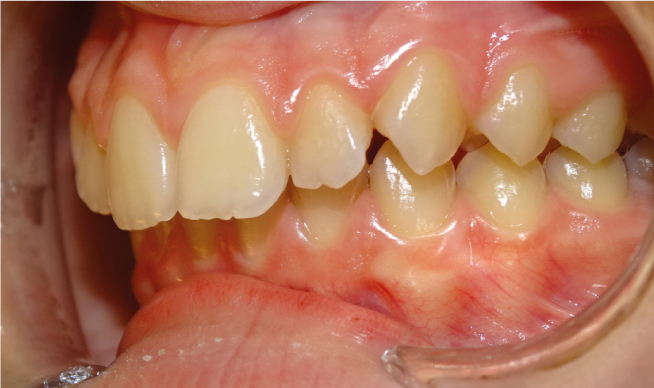

La classe II, c’est quand la mâchoire du bas est en arrière de la mâchoire du haut, donnant l’effet de “dents en avant” pour la mâchoire du haut. Si c’est normal à la naissance, Ceci paraitrait normal à la naissance et tend à se corriger avec l’allaitement maternel et la recherche de contacts entre les incisives du haut et du bas. Au plus on intervient tôt, au plus la mâchoire du bas va rattraper la mâchoire du haut ; au plus on attend, au plus on reculera le haut sur le bas avec des conséquences sur l’esthétique du profil et la capacité ventilatoire nasale.

Dans le cas d’une Classe II :

• La lèvre du bas s’interpose entre les 2 mâchoires

• Le sourire est étroit, tendance à l’écrasement du bas du visage